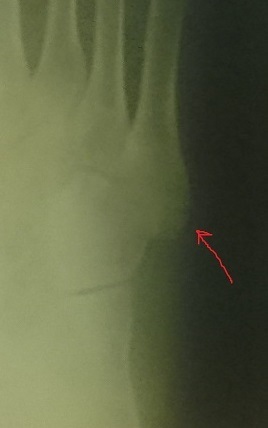

Вечером всё же заехал в местную ЦРБ(Центральная районная больница), где сразу же отправился к травматологу и коротко рассказав историю, попросил свою дозу рентгена. Травматолог Гогиашвилли (могу ошибаться, но вроде такая фамилия), как гордый орёл на вершине Кавказа, восседая на стуле, бросил уверенный взгляд на меня, и на расстоянии вытянутой руки поставил диагноз - "Перелома точно нет - с переломом не ходят, а ты целый день ходил. Разводи димексид один к трём, мажь гепариновой и найзом". В общем, мои воззвания, что может быть там и не перелом, а хотя бы трещина, и что может это я такой терпеливый - не возымели успеха. На свои кости я так и не посмотрел.

Думаю-ка, у меня же ДМС(Добровольное медицинское страхование) есть. Сказано - сделано. Записался по ДМС к травматологу аж на четверг, так как не было записи раньше. В назначенный час я уже разглядывал свой снимок в рентгене. Назначили мумие, остеомаг витрум, троксевазин гель, кетонал. Сказали, чтобы я этот снимок ткнул в морду врачам в ЦРБ.